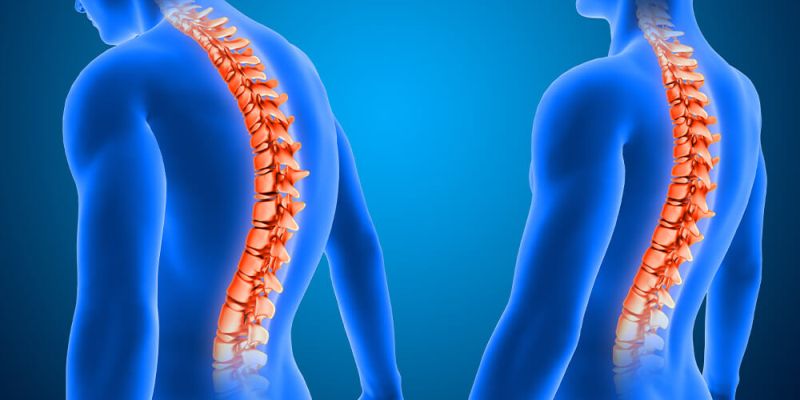

Kök hücre tedavisi

Yüzyılın tedavisi , ameliyatsız tedavi , Narkoz Yok , Ayni Gün Taburcu , %97 iyileşme garantisi , ülkemizde kök hücre tedavisini ilk yapan klinik biziz, dokuz yıldır bu tedaviyi başarı ile yapıyoruz.